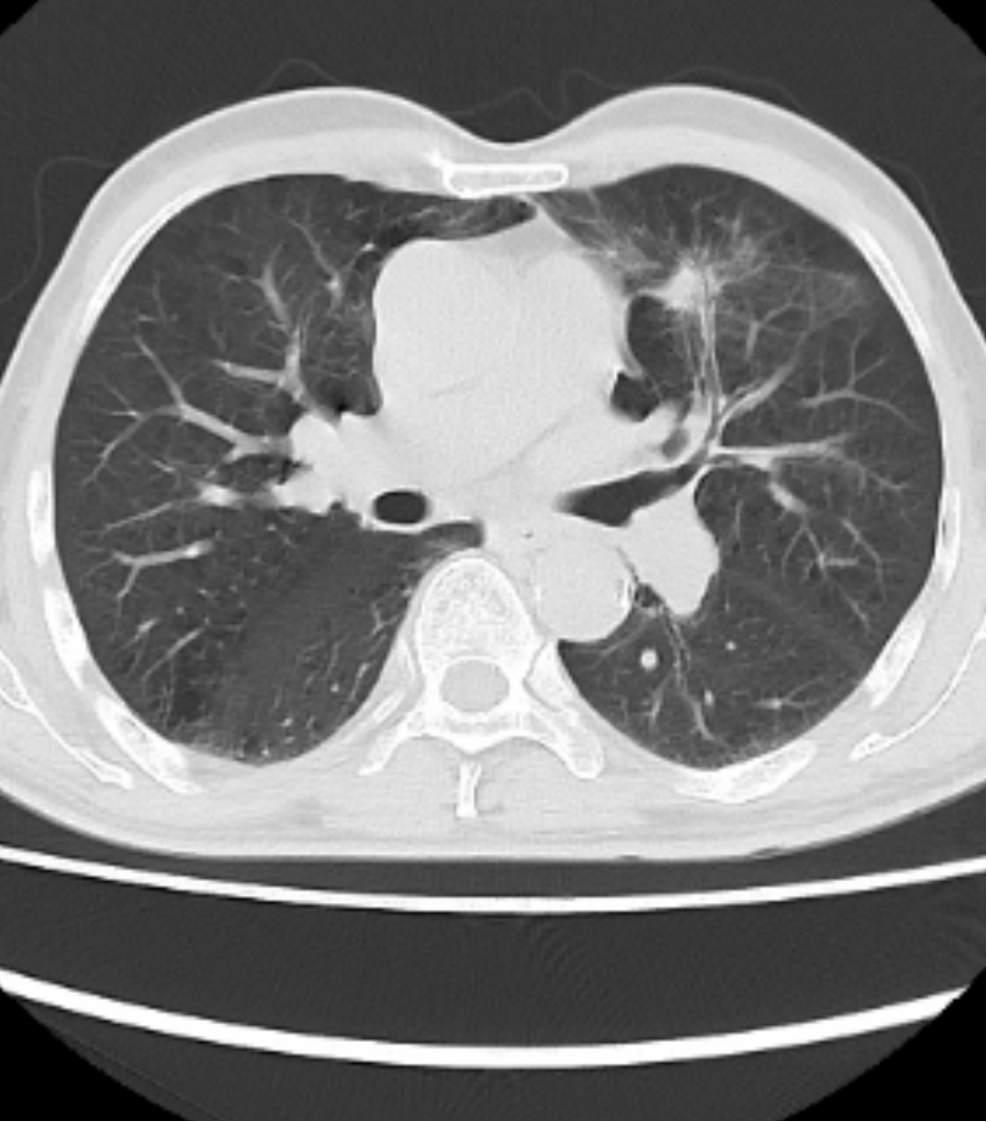

病例二:III期不可切除肺癌免疫轉化手術(shù)病例患(huàn)者,湯xx, 男(nán),63歲,發現肺癌4月餘,要求(qiú)手術治療。查體:生命體征平穩,心、腹(fù)未見明顯異常,胸廓對稱無畸形,雙肺叩診呈清音,聽診呼吸音粗,右上肺可及少許幹(gàn)囉音,餘肺部未聞及幹(gàn)濕囉(luō)音。輔助檢查:胸部CT示左肺上葉肺癌,縱膈及(jí)左肺門淋巴結腫大。入院診斷為左肺上葉腺癌,3.0x3.5 cm, 對(duì)側縱膈淋巴結腫大,T2N3M0 IIIB期腺癌。患(huàn)者經皮肺穿刺病理示:(左肺)考慮(lǜ)浸潤性腺癌。基因檢測無靶點,免疫檢測(cè)PDL-1 95%。從(cóng)2023-6-21到2023-8-24行單藥免疫治療(信迪利單(dān)抗)4個療程後,複查胸部CT示腫瘤明顯縮小,淋(lín)巴節消失,轉化(huà)治(zhì)療成功。患者於2023-9-27在(zài)插管全麻下行單孔胸腔鏡下左上肺葉切除+縱膈(gé)淋巴清掃術。術後病理診斷:(左上肺葉)鏡下見局部肺泡上皮不典型增生(shēng),呈附壁結構(gòu),間質纖維組織增生較明顯,伴(bàn)多量淋巴細(xì)胞、漿細胞及不等量的泡(pào)沫樣細胞、多核巨細胞等浸(jìn)潤,結合臨床可(kě)符合治療後改(gǎi)變,僅見少許附壁生長結構為主的腺癌殘留。新輔(fǔ)助治療後評估:存活腫瘤細胞比例約5%,壞(huài)死比例0%,間質比例(包(bāo)括纖維化及炎症)約95%,炎症反應等級中度,(支氣管斷端(duān))未見癌累及。(第5組淋巴結)5枚,可見纖(xiān)維化(huà)、鈣化等治療後反(fǎn)應,均未見癌轉移(0/5)。(第7組淋巴結)4枚,可(kě)見纖維化等治療後(hòu)反應,均未見癌轉移(yí)(0/4)。腫瘤及淋巴結病理緩解達到MPR。

免疫治療後胸部CT

免疫(yì)治療後(hòu)胸部CT